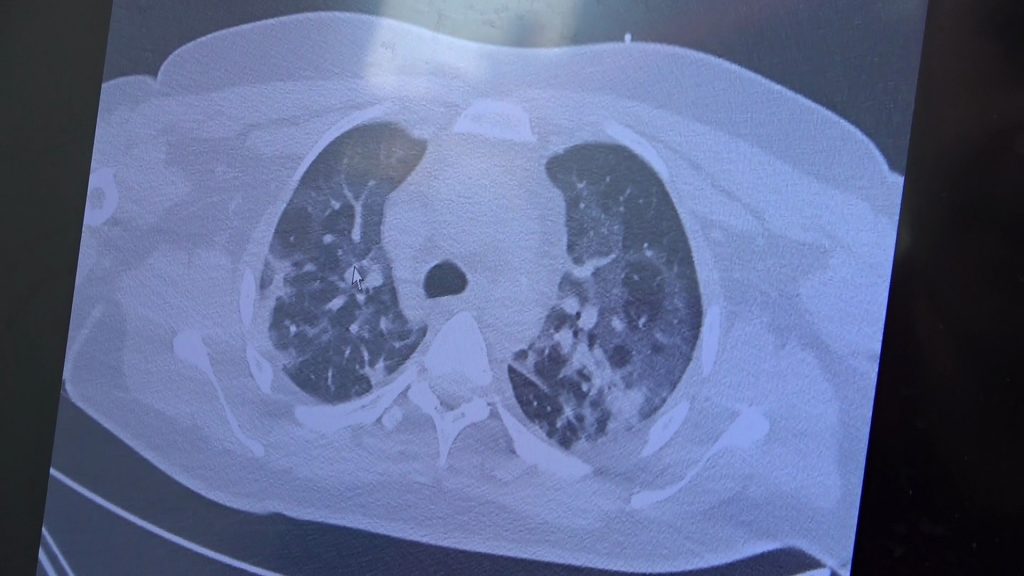

Gençlerin akciğer tomografilerini inceleyen Özkaya, “İki vaka örneği hakkında bilgi vermek istiyorum. İnsanlara bu işin bitmediğini anlatmamız lazım. 30 yaşında aşı olmamış bir hastamızın filminde çok yaygın akciğer hasarı var. Şu an kendisi yoğun bakımda tedavi alıyor. Öte yandan 25 yaşında bir hastamız var. İki doz kovid aşısını da olmamış. Ciddi akciğer tutulumları var. Çok ciddi solunum sıkıntısı ile kovid servisinde yatıyor. Şu an hasta profilimizin büyük bir kısmını bu durum oluşturuyor” ifadelerini kullandı.